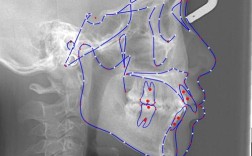

- X线头影测量分析:

- 头颅定位片的拍摄与描绘。

- 常用标志点、平面、角度、线距的测量与分析(如SNA, SNB, ANB, U1-SN, L1-MP, FH-MP, MP-SN, FMA, Y轴角, Wits值等)。

- 骨面型分析(I类、II类、III类)。

- 牙齿位置分析(突度、倾斜度)。

- 软组织分析(鼻唇角、E线、H线等)。